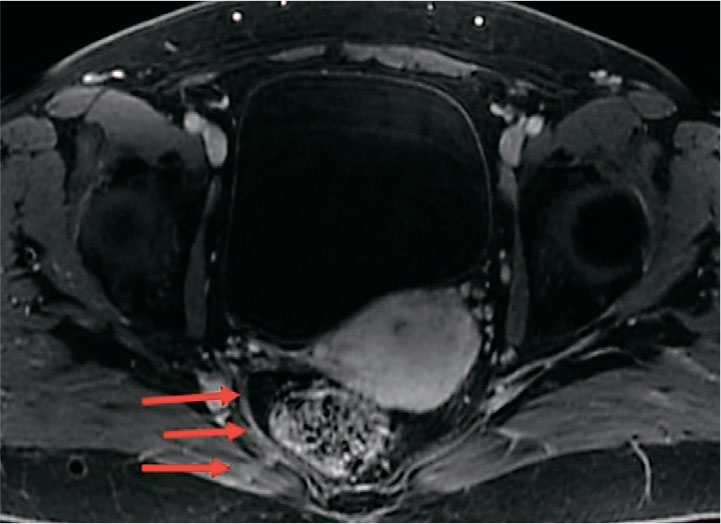

При выполнении МРТ органов малого таза с внутривенным контрастированием препаратом гадолиния спустя более 180 дней после оперативного вмешательства нити импланта с сформированным рубцом дифференцируется как тяж диаметром до 3-5 мм, следующий от сакроспинальной связки до шейки матки, без признаков отека на Т2-ВИ с подавлением сигнала от жира, с отчетливым равномерным накоплением контрастного препарата в позднюю венозную фазу, что характерно для рубцовой ткани (рис. 3-5).

Рис. 3. Пациентка Б. 56 лет. МРТ органов малого таза. Т1-ВИ с подавлением сигнала от жира после внутривенного контрастирования – поздняя венозная фаза. Рубец на уровне импланта справа отчетливо равномерно накапливает контрастный препарат (стрелки)

Fig. 3. Patient B, 56 years old. MRI of the pelvic organs T1-VI with signal suppression from fat after intravenous contrast late venous phase. The scar at the level of the implant on the right side clearly uniformly accumulates contrast agent (arrows)

Дополнительные данные, полученные при МРТ органов малого таза с контрастированием, подтвердили отсутствие признаков выраженной воспалительной реакции или хронического отека в зоне имплантации, что свидетельствует о хорошей биосовместимости частично резорбируемого материала, что также ранее было продемонстрировано в экспериментальном исследовании. Визуализация импланта позволила зафиксировать его интеграцию в ткани тазового дна и замещение резорбируемого компонента соединительнотканными структурами. Данный факт позволяет утверждать, что количество нерезорбируемого компонента достаточно для поддержания сформированной соединительнотканной неосвязки.